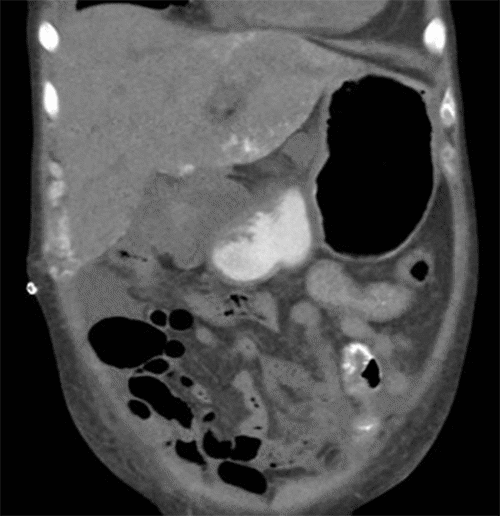

On POD 16, the patient developed severe left-sided abdominal pain with significant tenderness over her left flank and incision. She underwent an abdominal CT scan (Figure 1) and targeted biopsy of a calcified region of her allograft (Figure 2). Other studies demonstrated an elevated parathyroid hormone level (483pg/mL) with normal calcium levels, elevated phosphorous (6.8 to 7.6 mg/dL), and low vitamin D (17.9ng/mL). Given the initial concern for calciphylaxis, sodium thiosulfate therapy was initiated. The patient developed an upper GI bleed and underwent EGD, which showed hemobilia thought to be due to her recent liver biopsy. On POD 21, she developed worsening abdominal pain, hypotension, and tachycardia. Abdominal CT showed pneumoperitoneum, and she was taken to the OR for exploration. No source of pneumoperitoneum was found. She was subsequently noted to have a firm, pale liver, which was biopsied. On POD 40, our team discovered several firm subcutaneous nodules on her forearms, shoulders, and head (Figure 3).

Figure 1. Coronal CT Abdomen/Pelvis with Oral Contrast. Published with Permission

Heterogeneous calcifications involving the right upper quadrant (RUQ) liver periphery and adjacent abdominal wall are evident, near the incision site with visible skin staples. Additional findings include ascites and anasarca